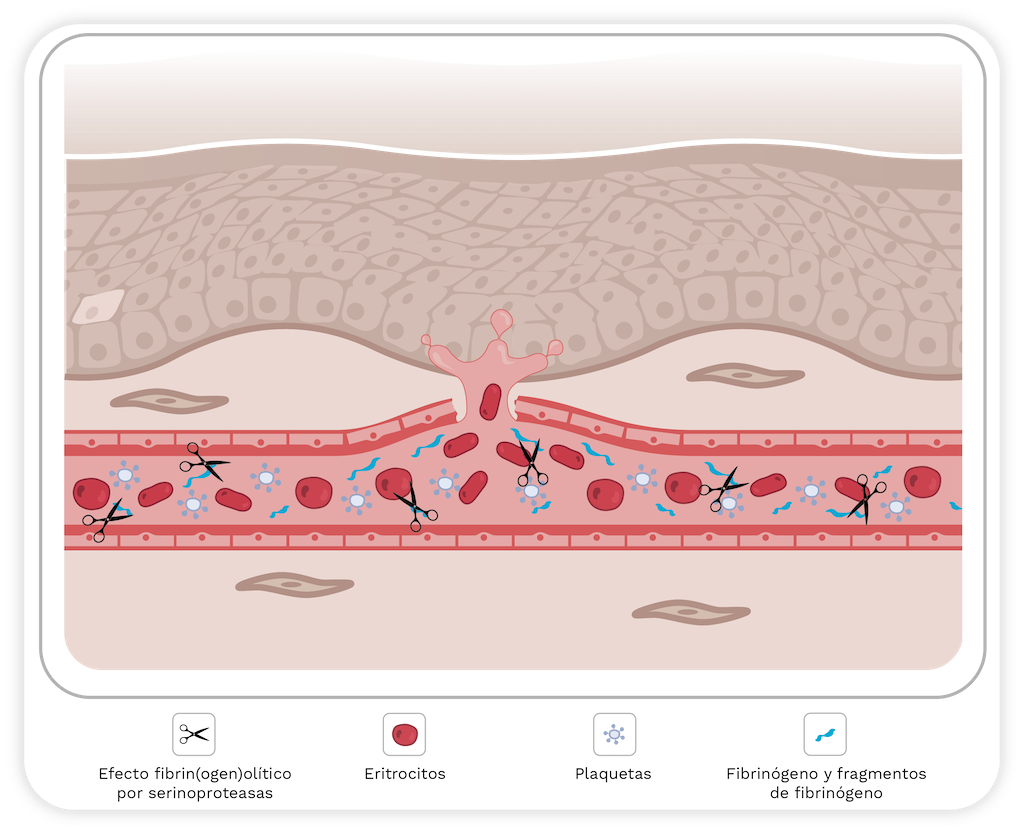

En el segundo paso, las fuerzas hemodinámicas actúan sobre la microvasculatura, incluida la tensión de corte y la presión hidrostática sobre la pared del microvaso. Estas fuerzas potencian la distensión de la pared, provocando su ruptura y la extravasación de glóbulos rojos [58] (Figura 5).

Figura 5. Representación esquemática del modelo de dos pasos para la hemorragia inducida por SVMP. El primer paso implica la hidrólisis de componentes de la membrana basal (MB) que desestabiliza la interacción entre las células endoteliales y la MB. En el segundo paso, las fuerzas biofísicas contribuyen a la potenciación de la distensión capilar de la pared de los microvasos, lo que lleva a su alteración. Para más detalles, consulte el texto. Imagen creada con Bio Render.

Hay dos tipos de hemorragia, por rexis y por diapédesis. La hemorragia por rexis es característica de la microvasculatura capilar. En este caso, la extravasación se produce a través de huecos formados en la pared del vaso, como se describió anteriormente. Además, el grosor de la célula endotelial disminuye, lo que debilita la pared capilar [52,53,64]. Aunque la hemorragia inducida por SVMP es causada principalmente por el modo por rexis, el mecanismo por diapédesis se observa en las vénulas donde los eritrocitos escapan a través de uniones intercelulares ensanchadas en lugar de a través de espacios en las células endoteliales [65].